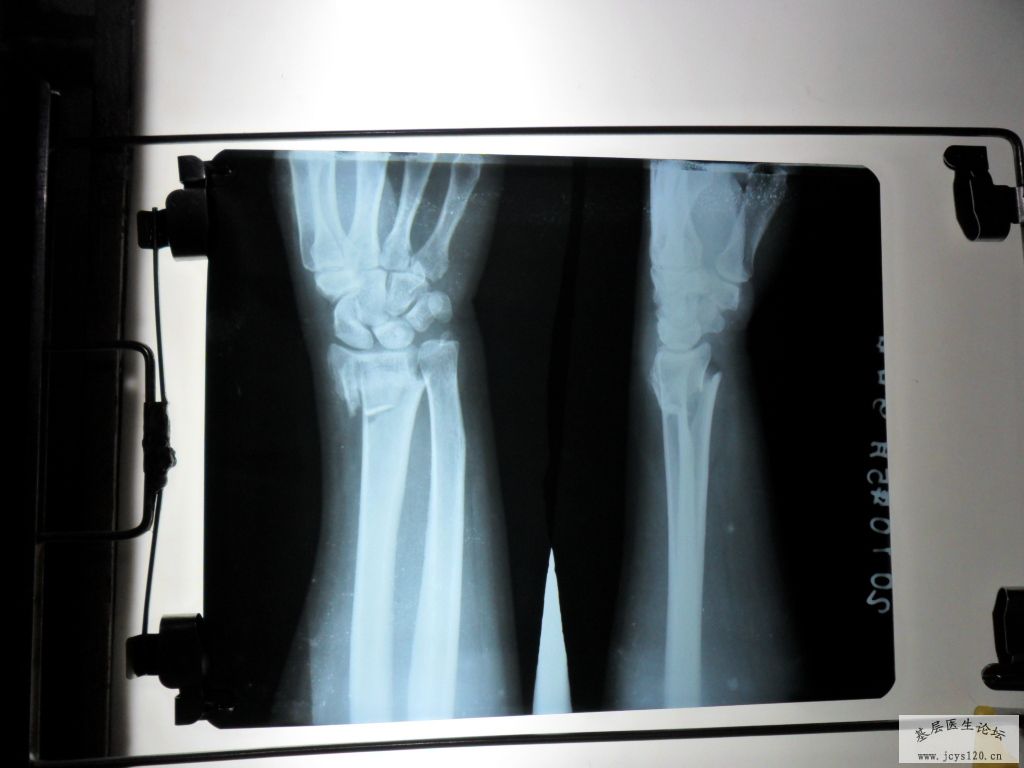

• 肘关节脱位伴骨折 attach_img

• jiangtaog123 2010-7-12

• 患者女35岁 ,高处坠落,左臂肘关节脱位伴桡骨头骨折,淤血凝结,青紫蛮重,痛疼剧烈。予以复位,以下是复位前后的片子 整复后外敷屈曲位固定,1骨肽针1合+NS250 GS250+脉络宁2支 ...  阅读全文>